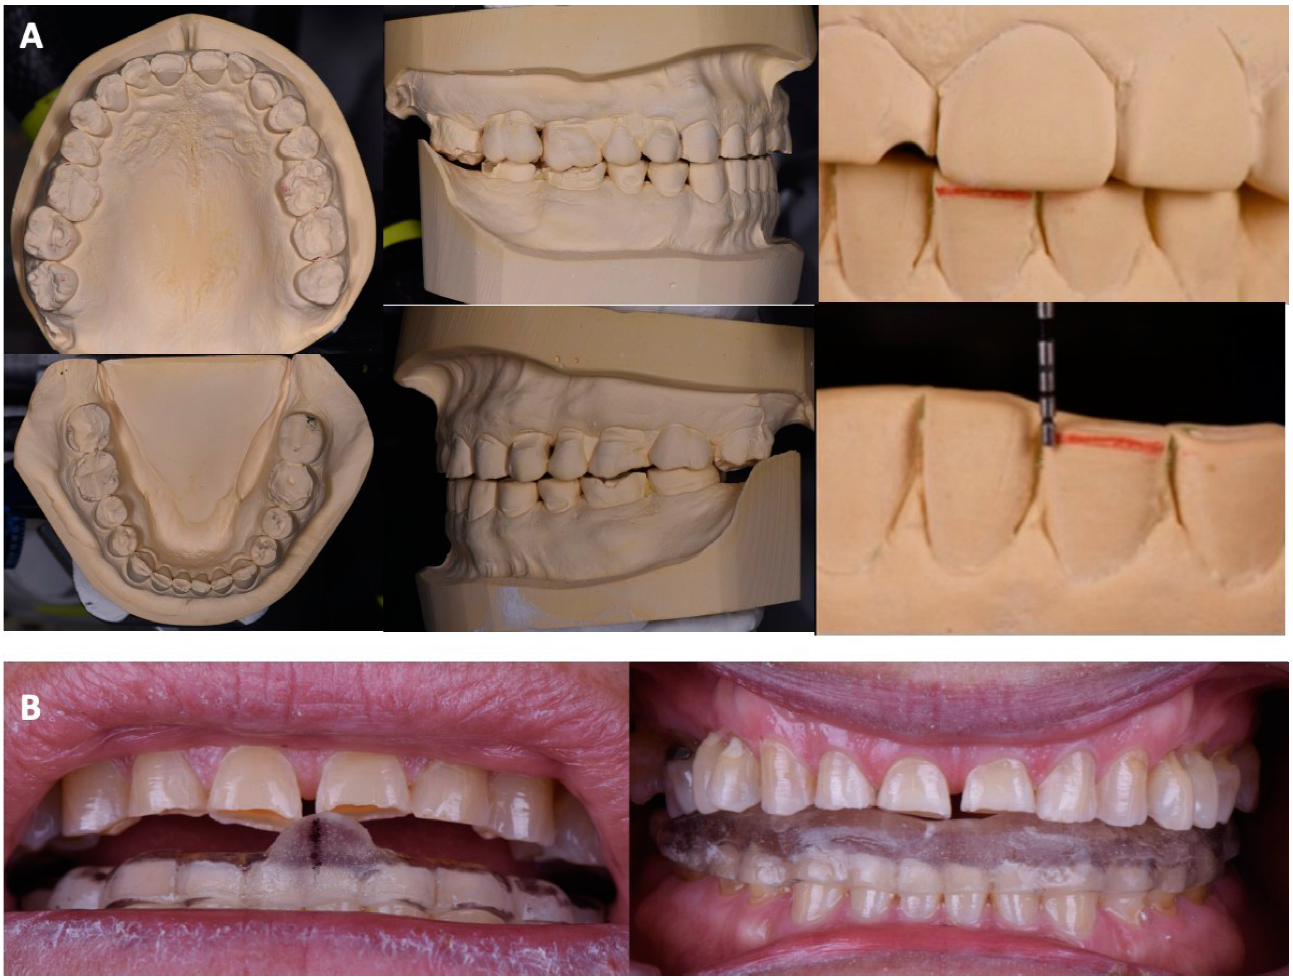

En el análisis oclusal, se observó relación canina y Clase I molar, sobremordida vertical 1mm y sobremordida horizontal 1mm, la DVO 61 y dimensión vertical en reposo (DVR) 66, el espacio libre interoclusal es de 5mm y la discrepancia entre máxima intercuspidación y relación céntrica es de 0.5mm (Figura 2A).

Figura 2 Análisis de los modelos y férula oclusal A. Análisis de los modelos, sobremordida vertical u oclusal (clasificación molar y canina). B. Procedimiento de fabricación de férula oclusal de 3.5mm para determinar adaptación a la nueva dimensión vertical de oclusión.

Mediante el encerado de diagnóstico, se optó por aumentar 3.5 la DVO en el vástago del articulador, propiciando un espacio adecuado para el material restaurador y dejando un espacio libre interoclusal de 1.5mm. Posteriormente se realizó una férula oclusal con 3.5mm de altura (Figura 2B), el paciente la utilizó durante 3 meses. Se comenzó retirando restauraciones defectuosas y lesiones cariosas (Figura 3A) en las cuales se colocó resin coating, para lo cual se utilizó grabado selectivo, adhesivo autoacondicionante (Single Bond 3MTM Espe, Alemania) y resina fluida (Filtek Z350 XT 3MTM Espe, Alemania) (Figura 3B). Una vez que el paciente confirmó la adaptación a la nueva DVO se procedió a probar el encerado en boca mediante un mock up (Protemp 3MTM Espe, Alemania), donde se evaluó: estética, fonética, plano oclusal, corredores bucales, oclusión, desoclusiones anteriores y aceptación del paciente (Figura 4A). Finalmente se procedió a la preparación de los dientes por medio de la maqueta pronóstica basada en el encerado para evitar desgastar más las piezas y preservando el espacio para el material restaurador. Las preparaciones consistieron en una corona completa del diente 37 con terminación en filo de cuchillo, carillas oclusales con biseles largos en los dientes 17, 16, 15, 25, 26, 27, 36, 46 y 47, vonlays en 14, 24, 35, 34, 44 y 45 así como carillas vestibulares en dientes anteriores mandibulares y preparación vertical de corona completa en dientes anteriores maxilares. Todas las restauraciones fueron elaboradas con e-max® Press High Transulcent (Ivoclar, Vivadent, Schaan, Liechtenstein) con técnica “Cut Back” en Carillas vestibulares y vonlays mientras que el resto de las restauraciones fueron maquilladas. Al momento de la cementación las carillas oclusales fueron acondicionadas con gel de ácido fluorhídrico débil 9.5% (Porcelain Etchant, Bisco Inc., Schaumburg, IL, Estados Unidos) durante 20 segundos, se lavó, se colocó ácido fosfórico al 35% con 60 segundos de fricción para eliminar residuos, seguido por un lavado de 20 segundos. Se secaron y se colocó silano (Clearfil ceramic primer, Bisco Inc., Schaumburg, IL, Estados Unidos) el cual se dejó secar por 60 segundos. Posteriormente se colocó adhesivo Universal (Clearfil Kuraray, Kurashiki, Japón) y cemento dual (Panavia V5 A2 Kuraray, Kurashiki, Japón).